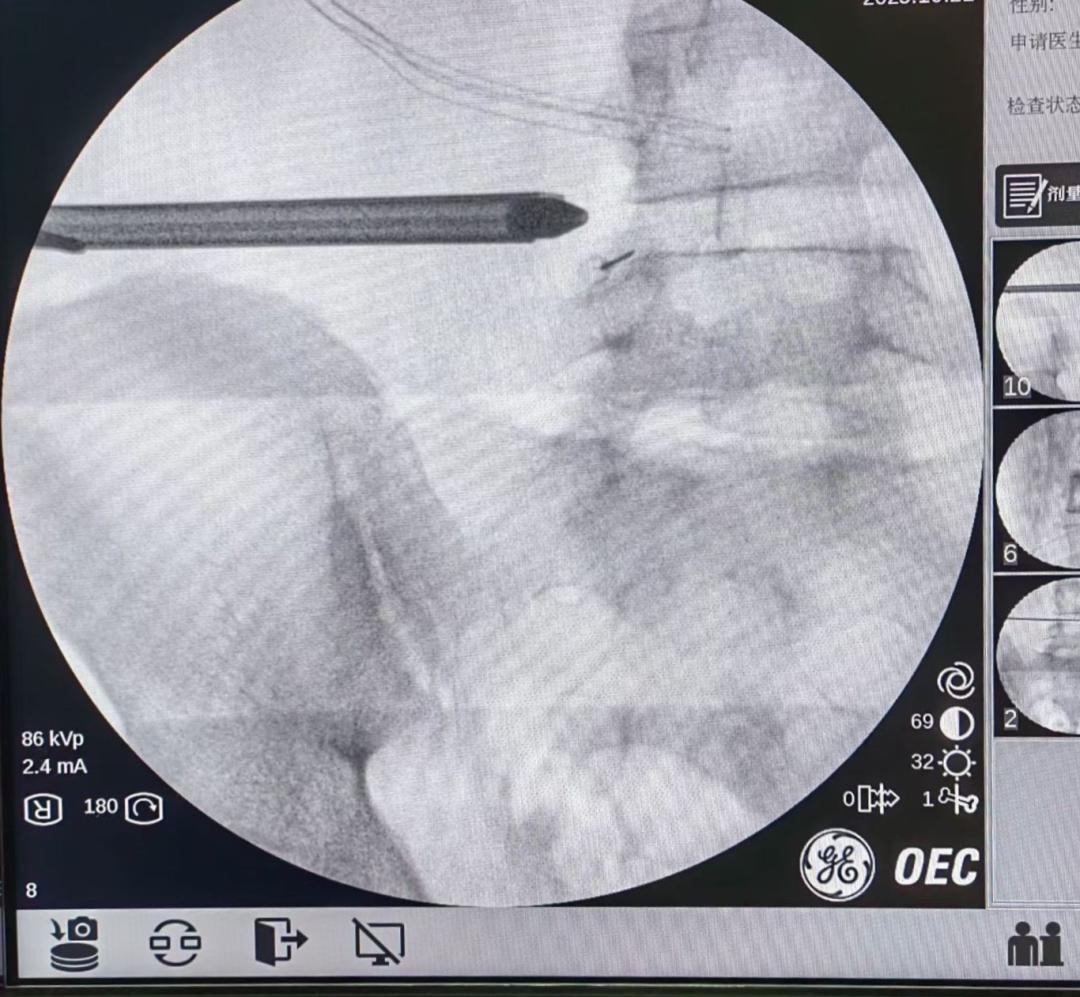

术中,主刀医生李主梅凭借丰富的操作经验,将工作通道精准置入,在高清内镜视野下,清晰辨识突出间盘、神经根及硬膜囊关系。

通过特殊角度和技术手法的巧妙运用,将巨大突出的髓核组织彻底摘除,并延伸至对侧,成功解除双侧神经根压迫,椎管容积恢复正常。